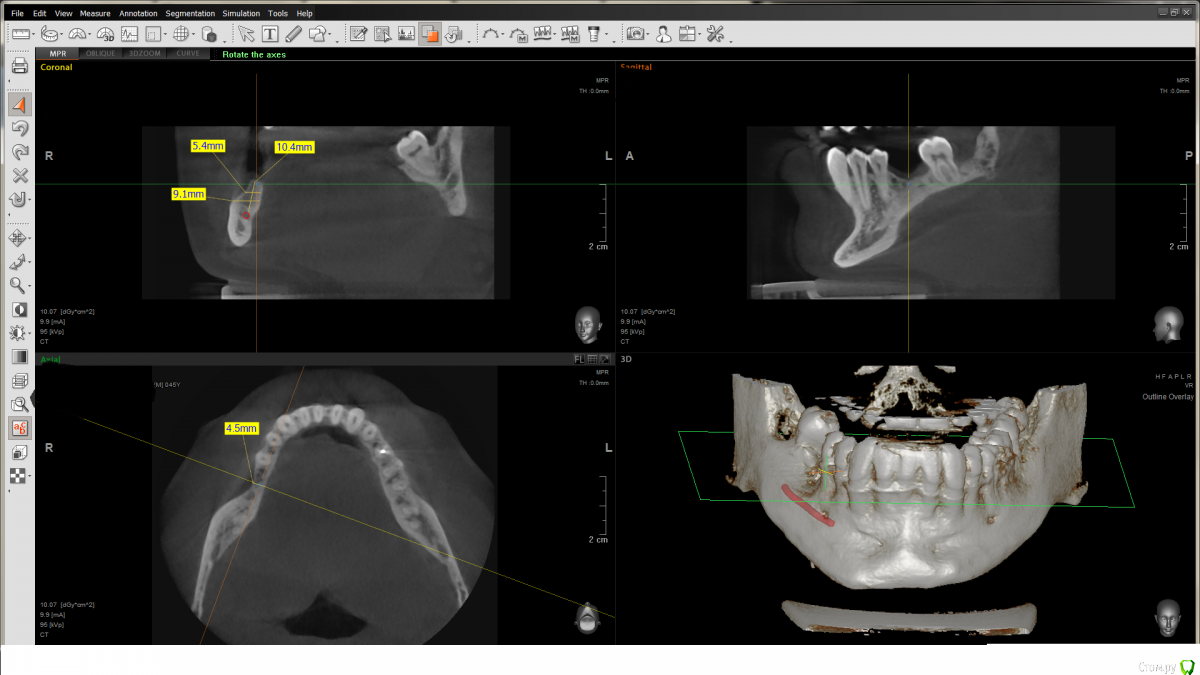

shy Опубликовано 15 августа, 2019 Поделиться Опубликовано 15 августа, 2019 (изменено) Добрый день ,коллеги .Только начинаю свой путь в имплантологии , прошу Вашего советаОбратился пациент ,в анамнезе 46 удален 6 месяцев назад,имеем что имеем. Как бы вы решили данную клин.ситуацию . работает клиника имплантатами Osstem .в голове - установка импланатата Osstem 4.0x8.5 , вестибулярно либо коллагеновая мембрана с миксом 50-50 аутоксено по штайгману ,либо взять Osstem смартбилдер .подскажите как бы вы решали ситуацию . Заранее спасибо Изменено 15 августа, 2019 пользователем shy Ссылка на комментарий

voff Опубликовано 23 августа, 2019 Поделиться Опубликовано 23 августа, 2019 (изменено) Имплант 10 и коллагеновая мембрана с графтом, соединительная ткань сверху .п.с. на кт нерв не нерв имхо Изменено 23 августа, 2019 пользователем voff Ссылка на комментарий

shy Опубликовано 23 августа, 2019 Автор Поделиться Опубликовано 23 августа, 2019 Имплант 10 и коллагеновая мембрана с графтом, соединительная ткань сверху .п.с. на кт нерв не нерв имхо на кт это точно нерв .ниже bone marrow deffect Ссылка на комментарий

shy Опубликовано 26 августа, 2019 Автор Поделиться Опубликовано 26 августа, 2019 Тогда уж крутили бы 3.5 и не парились с нкртак там 4.8 мм ширина гребня ,я пока что ориентируюсь на лит.ру с рекомендациями 1.5 мм с вестибулярной\язычной стороны. Ссылка на комментарий